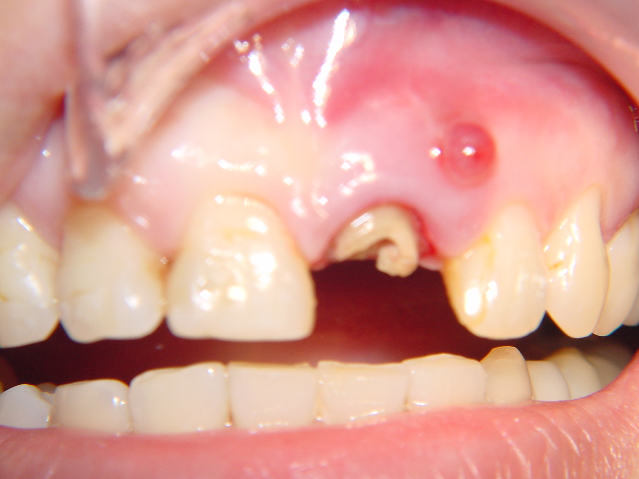

(1) 35歲女性,左上正中門牙牙根斷裂,在頰側有膿胞

(3)手術當天

i)小心拔除斷裂的牙根後,做牙冠延長術;定位將來預定的牙齦高度,將植體依正確位置放入。

ii)鎖上cover screw,轉移顎側肉瓣;測試primary closure的可能性;補上自體骨及DFDBA並縫合。